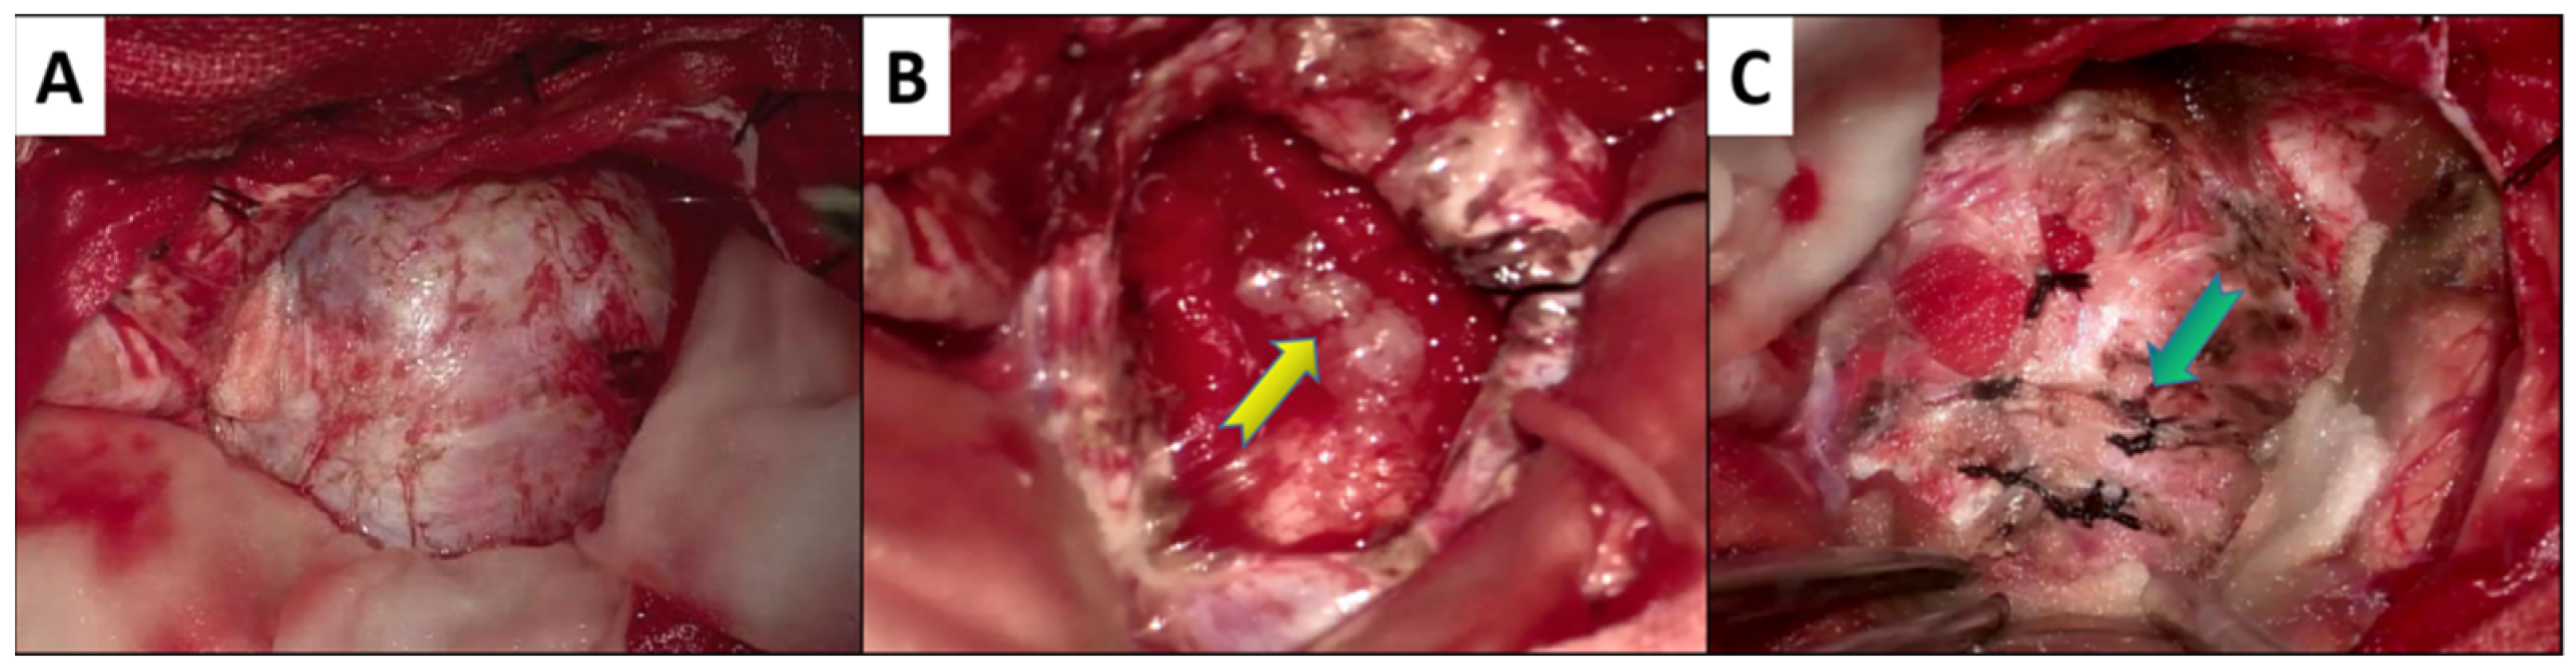

3.3. Surgical Resection

3.4. Histopathology